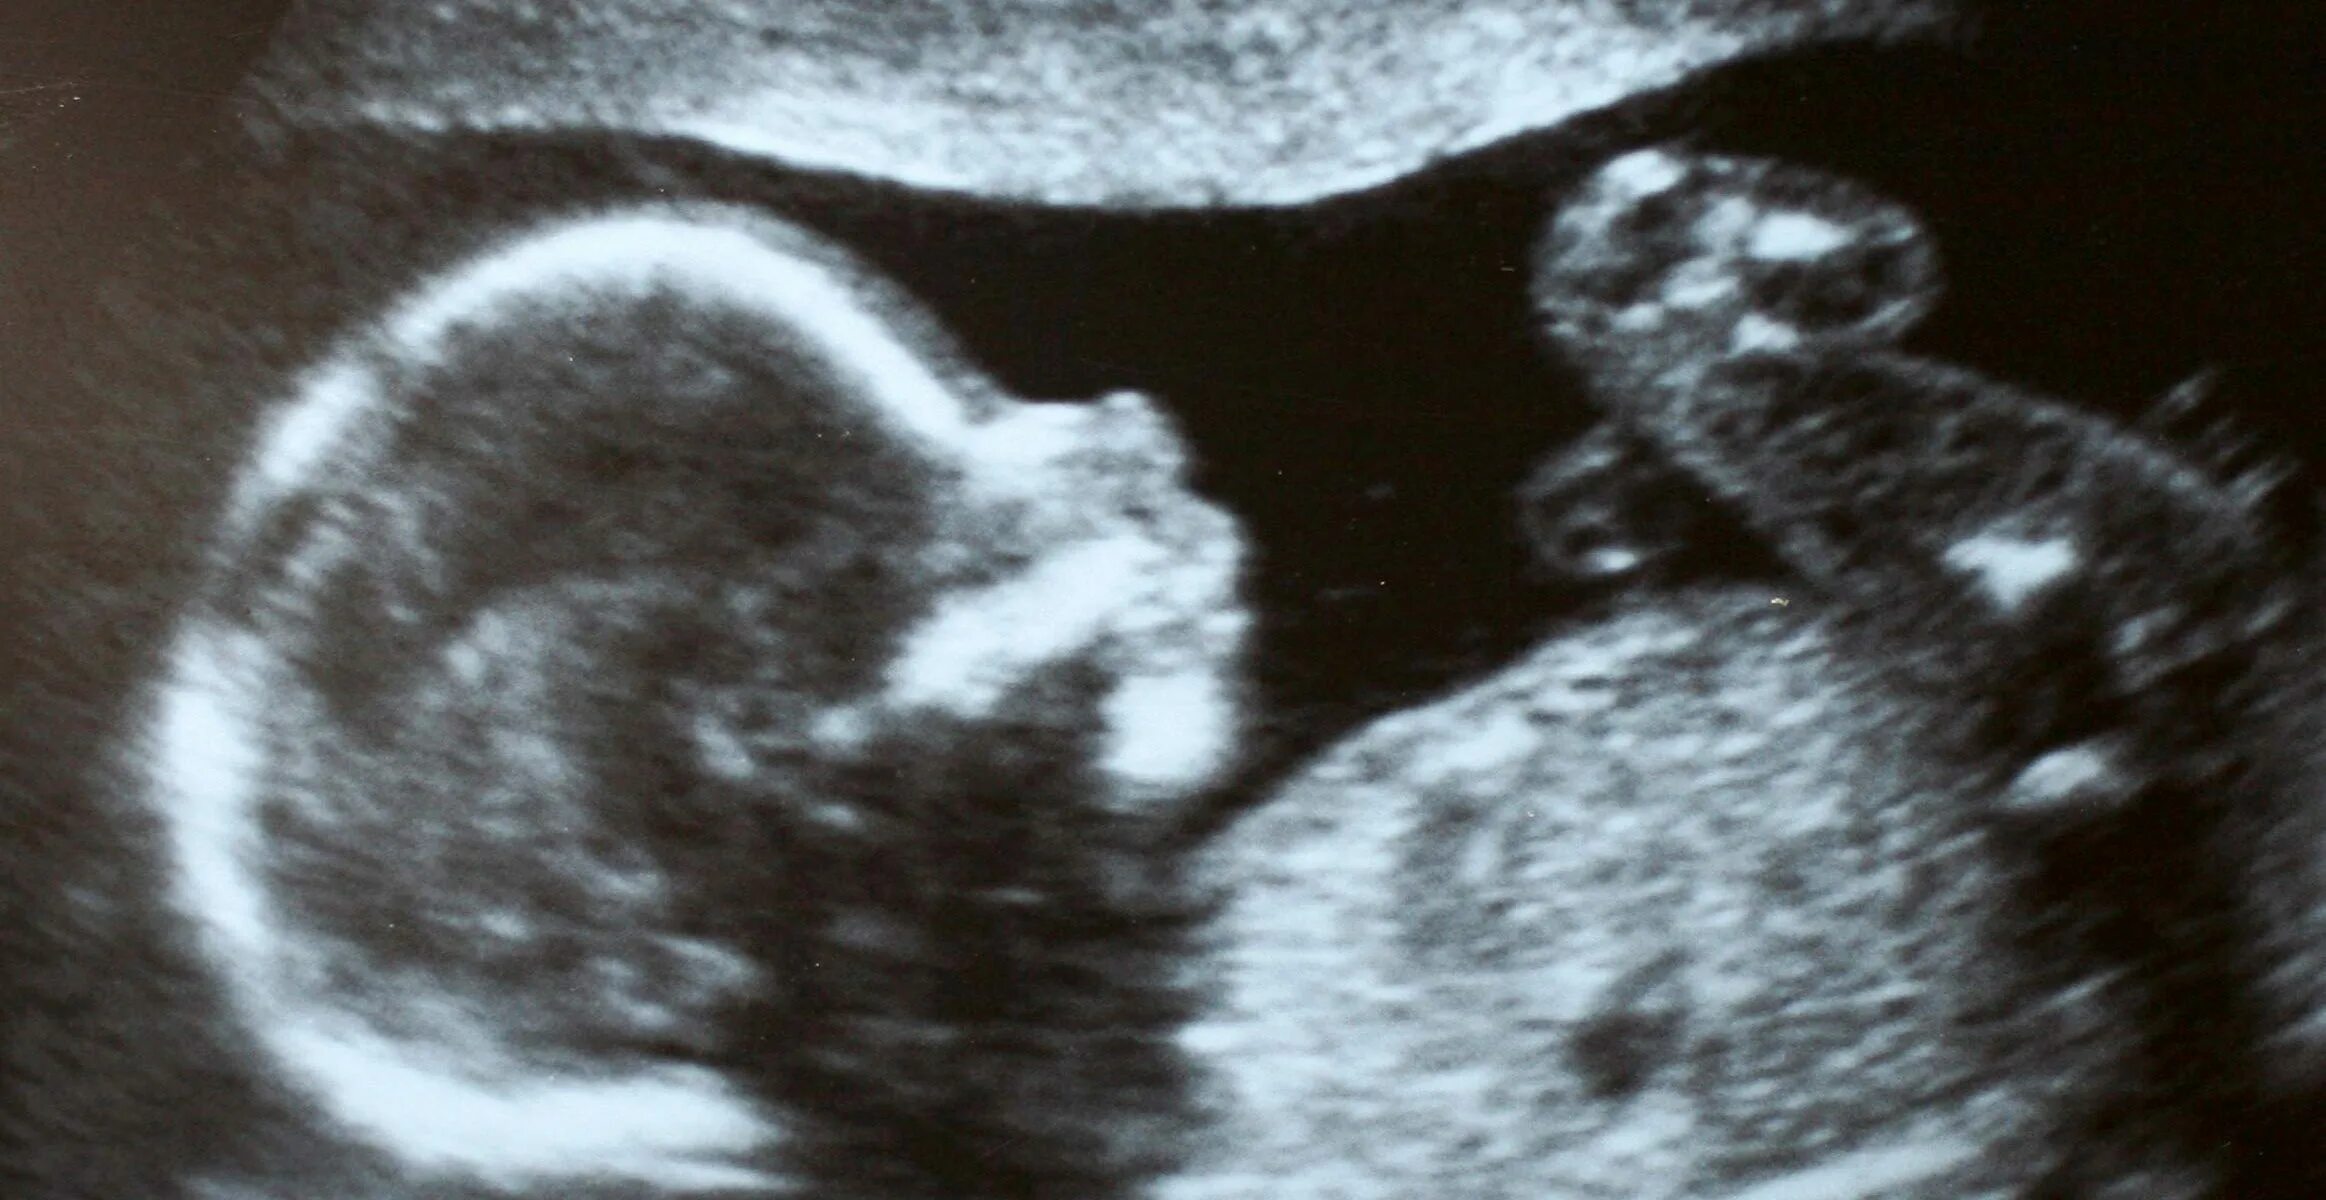

Второй скрининг 21 неделе